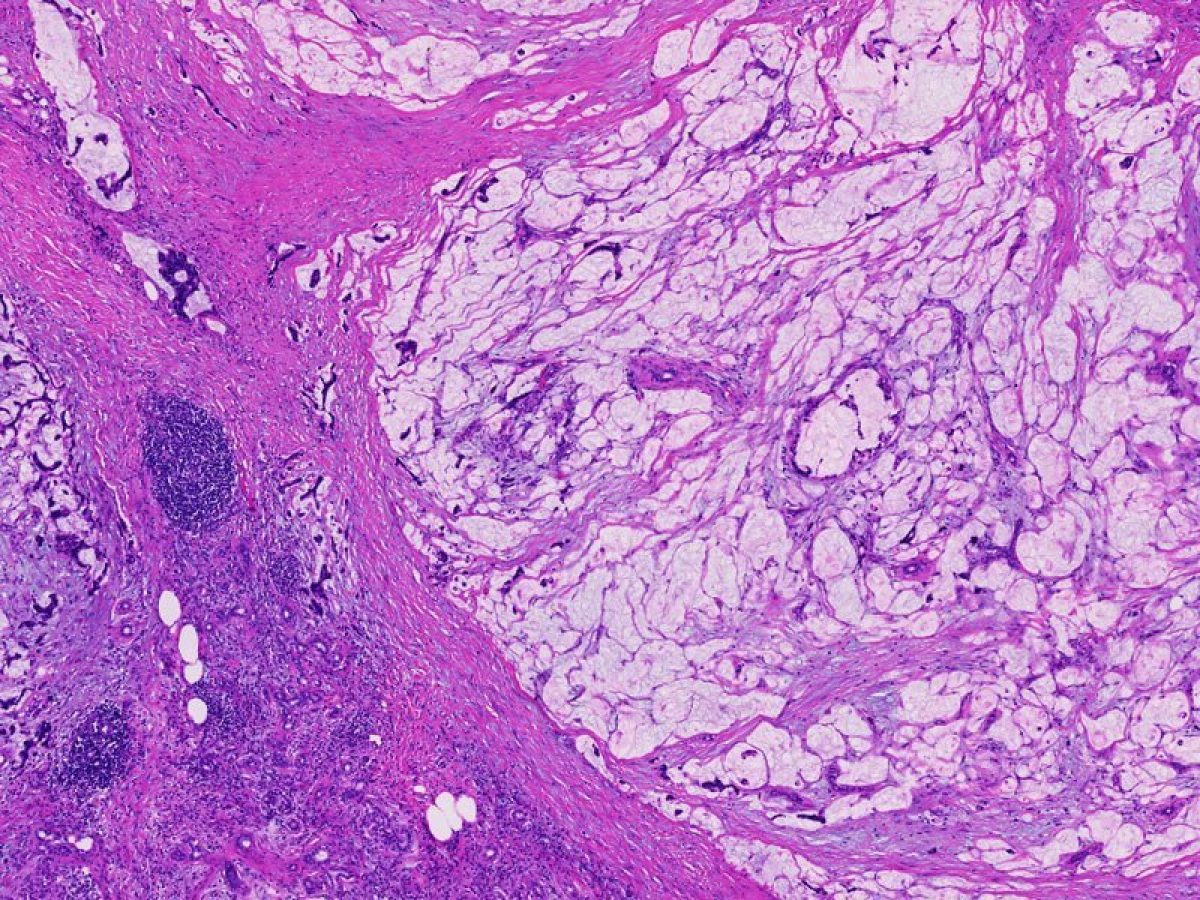

A fluid filled sac. Some tumors of the pancreas, including the serous cystadenomas and intraductal papillary mucinous neoplasms, form cysts. Cysts have a distinct appearance in CT scans. They are important to recognize because the treatment of cystic tumors can differ from that for solid tumors.

Tumors which are non-cancerous. These generally grow slowly and do not invade adjacent organs or spread (metastasize) beyond the pancreas.